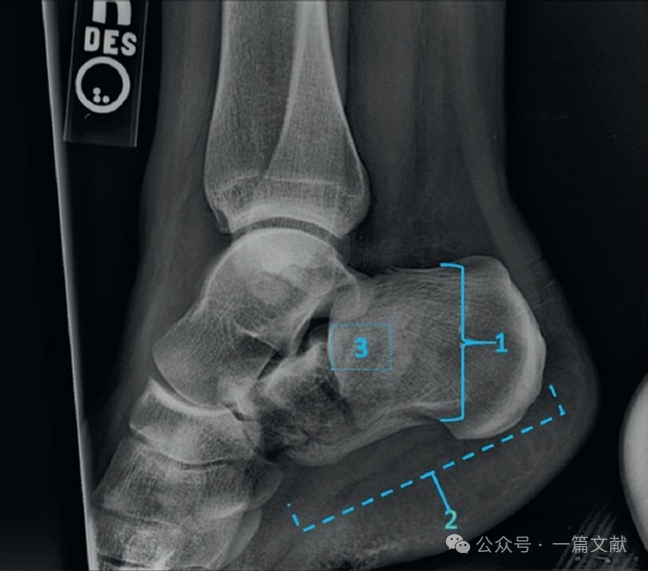

3.1 跟骨侧位片:可观察Bohler’s角,Gissane角,后距关节面情况,以及跟骨结节的移位情况,如下图:

可用于评估(1)跟骨高度,(2)跟骨长度,以及(3)后距关节面的受累,如下图: